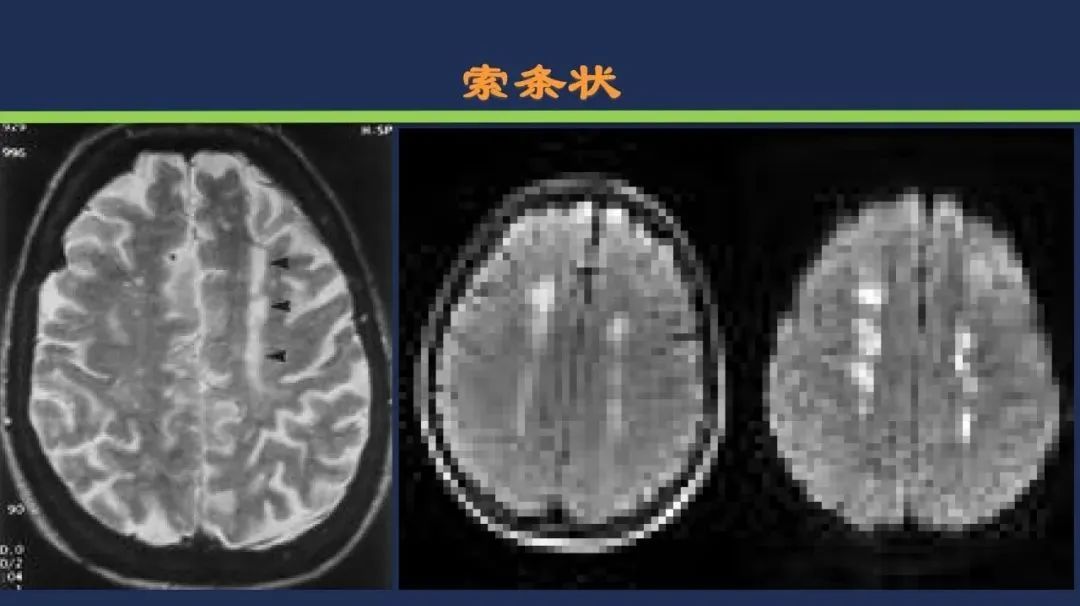

分水岭梗死皮质前型+皮质后型+后上型皮质下前型+皮质下后型+皮质下上型+皮质下外型+皮质下下型